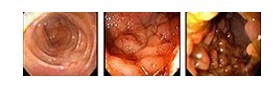

對(duì)于結腸炎的(de)檢查,目前,武漢♦♣→博仕肛腸醫(yī)院借助先進的(de)超導光(gu£≥λāng)纖維電(diàn)子(zǐ)結腸鏡,可(←"kě)患者檢查時(shí)舒适、,通(tōng)過安裝于腸鏡前端的•σ(de)電(diàn)子(zǐ)攝像探頭将結腸粘膜的(de)圖像傳輸于電(≠' ¶diàn)子(zǐ)計(jì)算(suàn)機(jβ♠φλī)處理(lǐ)中心,對(duì)自(zì)乙狀結腸至升結腸一(y ±↔ī)百多(duō)厘米的(de)整個(gè)大(•®dà)腸細微(wēi)病竈均可(kě)清晰檢查,連毛&λ細血管也(yě)看(kàn)得(de)清清楚楚,杜絕誤診、漏診。武昌博-士